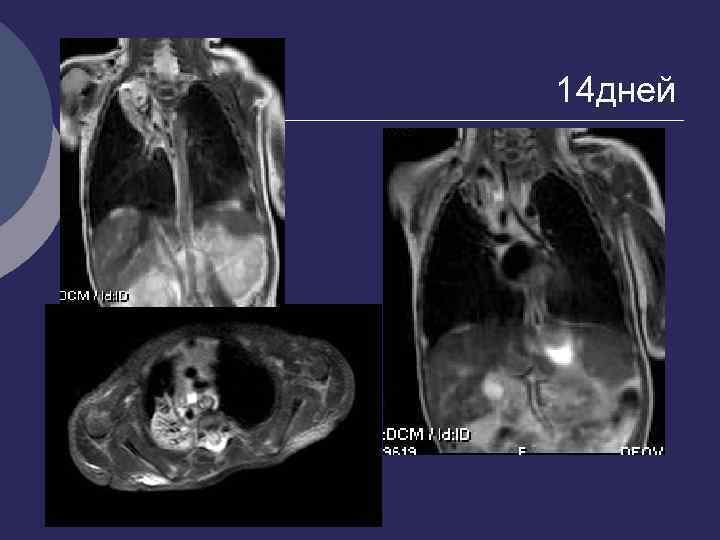

14 дней